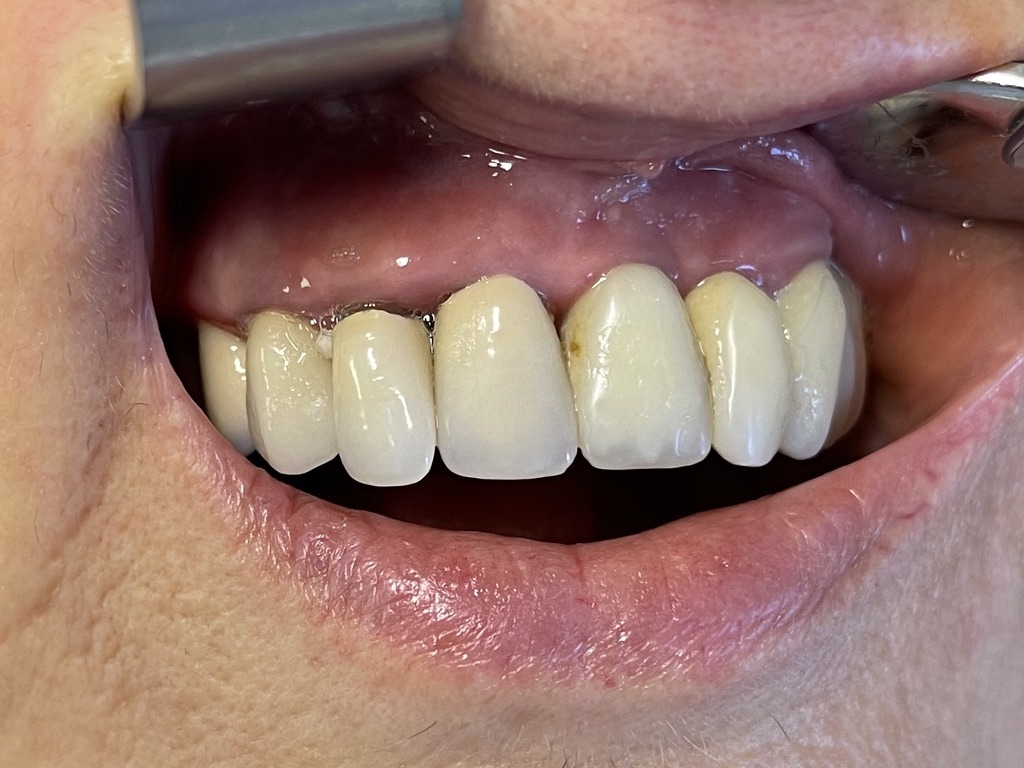

2 - ESTETICA E FUNZIONE NELL'IMPLANTOLOGIA UMANA

Sulla perfezione estetica...